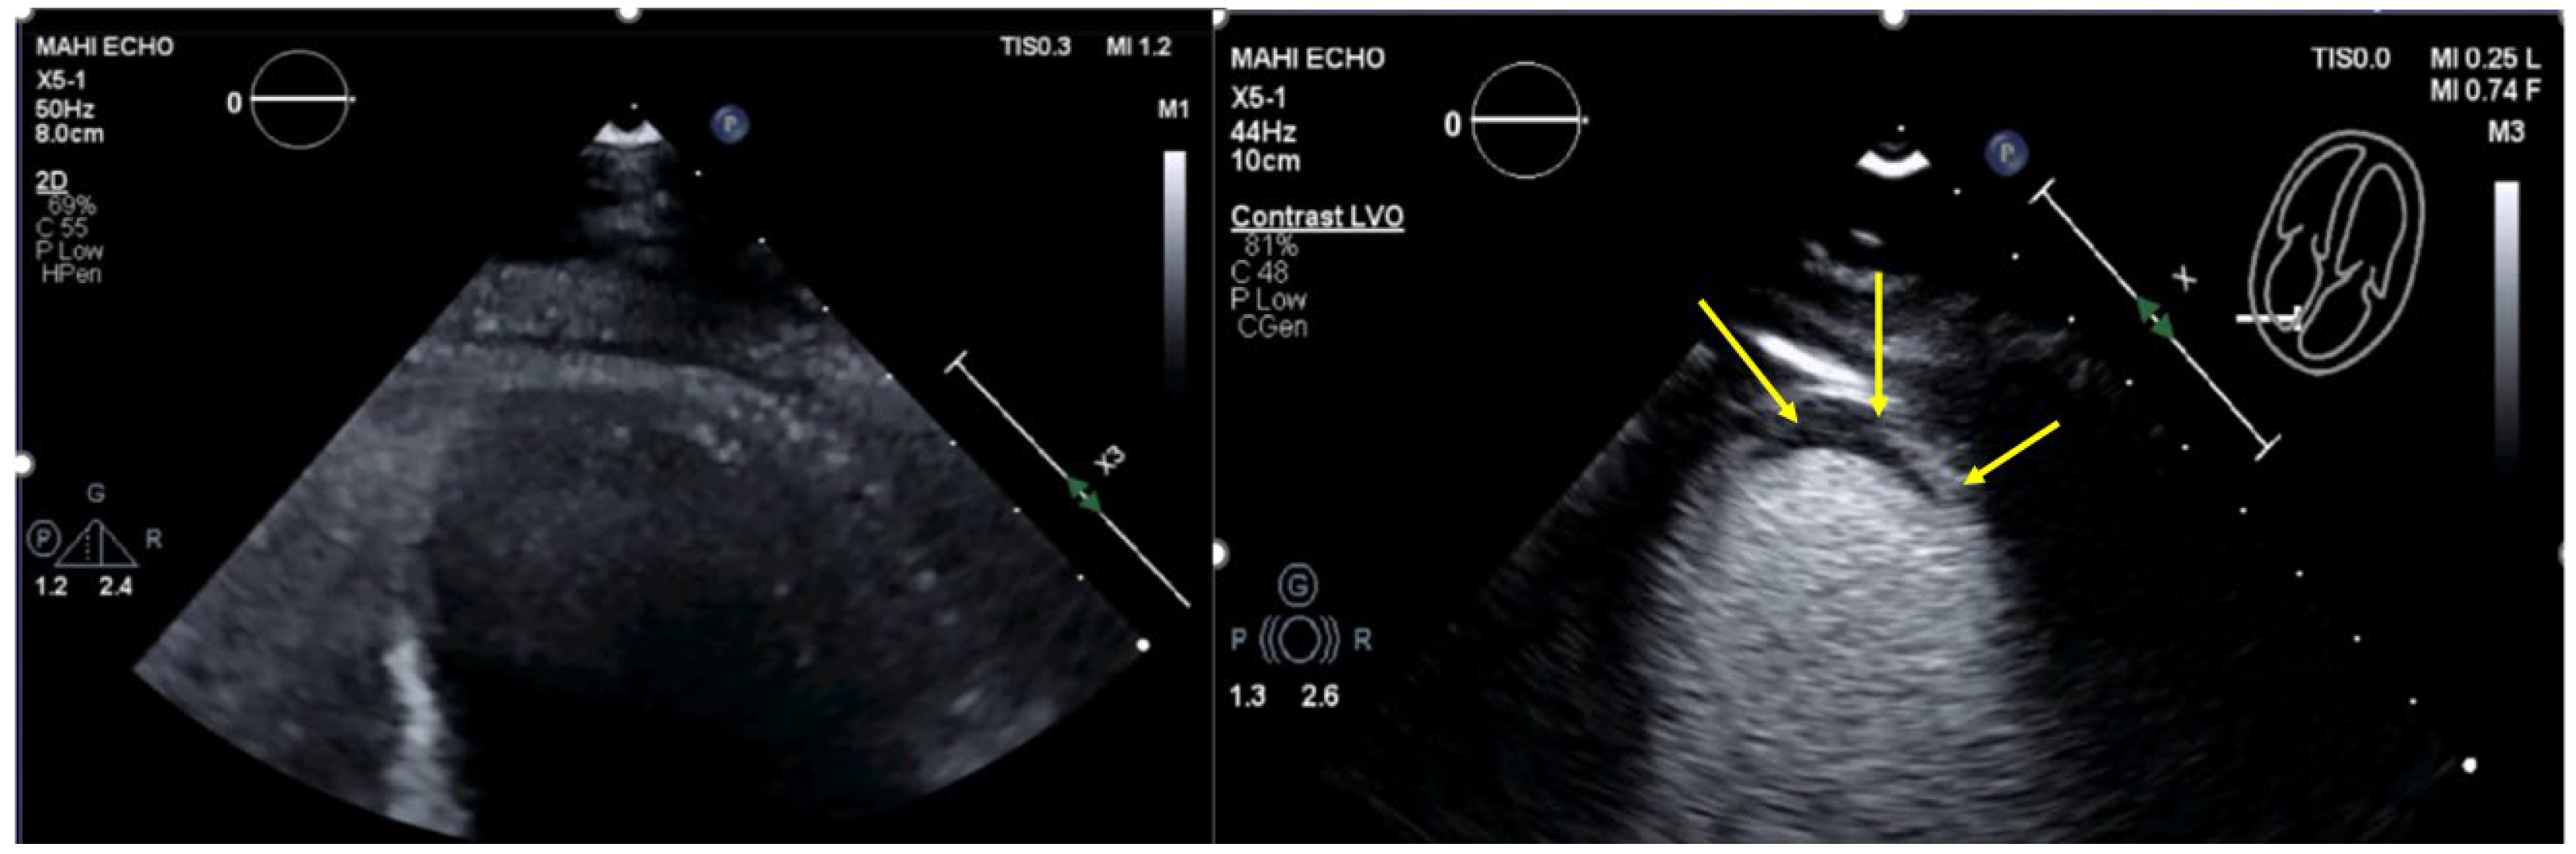

| Imaging method | Low-MI-contrast-specific imaging and intermediate-MI-contrast-specific imaging |

| Imaging planes | standard apical views additional zoomed views sweeps through the region of the suspected thrombus |

| Sector depth/width | Entire LV + 1/3 LA to assess global/regional LV function, zoomed views of the region with the suspected thrombus |

| Focus | At the depth of the suspected thrombus |

| Gain | Adjust to avoid obscuring the thrombus by intensive opacification of the cavity |

| Contrast application | bolus injections |

| Typical findings | 1. echofree mass 2. present in two different imaging planes 3. lump or laminar shape different from trabeculations’ documented size (two orthogonal diameters in at least one of the views), location, type (laminar vs. lump, single vs. multiple), surface (smooth vs. irregular) and mobility |

| DD tumor vs. thrombus | Opacified (vascularized) masses are suggestive of tumors; the vascularization can be demonstrated with myocardial perfusion imaging. CAVEAT: There are malignant tumors which appear avascular on CEUS. Tumors often are attached to normal myocardium. |

| Alternative imaging | Thrombi: Cardiac MRI when contrast echo is not possible or non-diagnostic, cardiac CT when cardiac MRI is not available Tumors: MRI provides tissue characterization and should be performed unless there is typical myxoma (attached to the interatrial septum) |